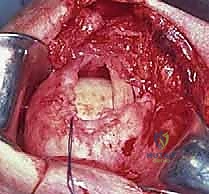

يتم تحضير "بصمة الوتر" (Footprint) على رأس عظم العضد عن طريق تقشير العظم بلطف لتعزيز النزيف الخفيف الذي يجلب الخلايا الجذعية وعوامل النمو لتسريع التئام الوتر بالعظم.

ثم يتم زرع خطاطيف جراحية (Suture Anchors) متطورة (مصنوعة من التيتانيوم أو مواد قابلة للامتصاص) داخل العظم.

هذه الخطاطيف متصلة بخيوط جراحية فائقة القوة. يقوم الدكتور هطيف بتمرير هذه الخيوط عبر الوتر الممزق باستخدام تقنيات خياطة معقدة (مثل صف مزدوج Double Row) لضمان توزيع الضغط وتوفير تثبيت ميكانيكي صلب.

يتم ربط العقد الجراحية بإحكام، ويتم اختبار حركة الكتف على طاولة العمليات للتأكد من متانة الإصلاح وقدرة الوتر على تحمل الشد.